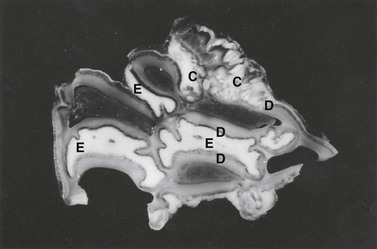

Complex odontoma presents as a radiodense calcified lesion within the jaw of young horses. Grossly, they are very hard and difficult to prepare for histological examination. Cut surfaces reveal variegated cementum, dentin, and mineralized enamel (Fig. 11.10).34 The gross features are confirmed histologically, and there can be variable amounts of odontogenic epithelium. In the horse, there is plentiful cementum.

image

Fig. 11.10 Undecalcified thick section of a complex odontoma in a 2-year-old Morgan colt. Well-differentiated but disorganized components of tooth formation are shown. D, dentin; C, cementum; E, enamel.

(Reproduced with the kind permission of Dr R.R. Dubielzig and Iowa State Press.)